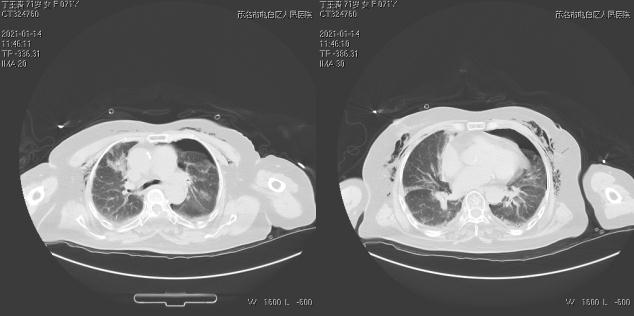

第二天,在李文峰副院長指導(dǎo)下再次行右側(cè)胸腔閉式引流術(shù),過程順利。經(jīng)過綜合處理,患者恢復(fù)良好,轉(zhuǎn)危為安,家屬露出了滿意的笑容。

術(shù)后CT